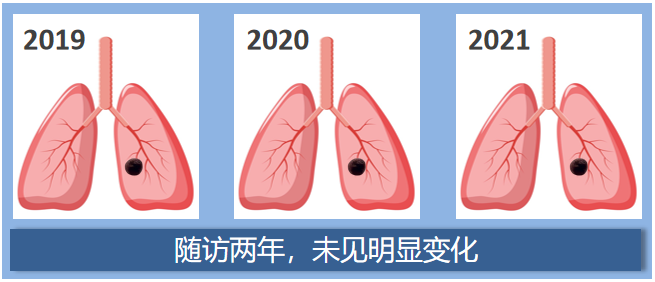

这是大家最关心的事了,我们来看几组肺结节随访病例模式图。

第一组:实性结节

患者1:2019年左肺发现一枚实性肺结节,两年后CT复查,肺内的这枚实性结节大小和形态没有明显变化。